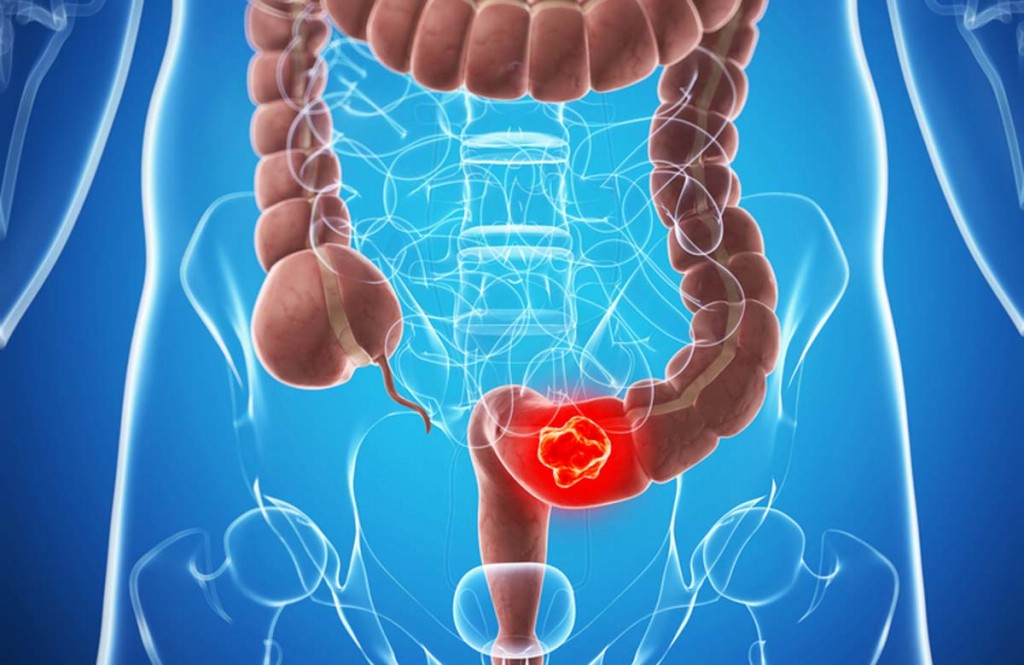

Os Principais Sintomas de Câncer Colorretal que todos devem ficar atentos. Além disso, o Câncer Colorretal é um tipo de câncer onde as células anormais se formam no cólon ou no reto. O Câncer Colorretal e câncer de reto geralmente são agrupados porque o cólon e o reto compartilham características comuns como partes do sistema gastrointestinal.

A grande maioria de Câncer Colorretal se formam nas glândulas produtoras de muco (adenocarinomas) dentro do cólon ou reto e se desenvolvem ao longo de vários anos. Geralmente, eles começam como pequenos grupos de células benignas (não cancerosas) no cólon conhecido como pólipos.

Além disso, tumores menos comuns que podem se formar no cólon ou no reto são tumores estromáticos gastrointestinais e linfomas. Então, confira Os 10 Principais Sintomas de Câncer Colorretal:

Prognóstico do Câncer Colorretal: Se você foi diagnosticado com Câncer Colorretal, suas opções de tratamento variam e dependerão do estágio do câncer. Os três tratamentos primários são cirurgia, quimioterapia e terapia de radiação.

Para Câncer Colorretal em estágio inicial, onde o câncer é isolado em um pólipo, um pequeno procedimento cirúrgico durante uma colonoscopia pode remover completamente todas as células cancerosas. Pólipos maiores podem ser removidos usando a cirurgia laparoscópica. Para um Câncer Colorretal mais invasivo, seu médico pode recomendar qualquer um dos seguintes:

- A ressecção é um procedimento usado se o câncer se espalhou pelas paredes do reto. Nela, a seção cancerosa do reto é removida, juntamente com alguns tecidos saudáveis próximos.

- A colectomia é uma cirurgia para remover a parte do cólon que contém o câncer, bem como alguns tecidos próximos.

- A excisão local do reto é a remoção de porções cancerosas do reto.

- A exenteração pélvica é a remoção do cólon, do reto e da bexiga inferiores, bem como da próstata nos homens e do colo do útero e ovários nas mulheres. Este procedimento é usado apenas se o câncer se espalhou para esses outros órgãos.